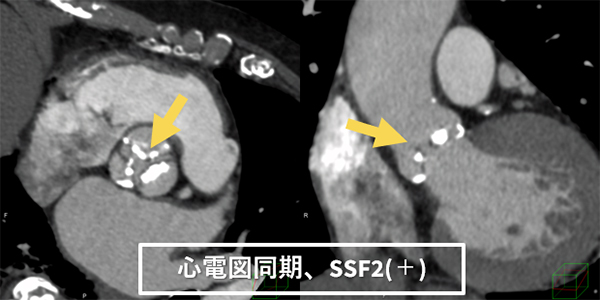

図5 TAVI 術前計測CT

装置更新前はTAVI術前の大動脈弁計測において、モーションアーチファクトのある状態で計測することが多かった。Revolution CTにおいても、管球回転速度は上昇したが、弁が最大拡張した位相でモーションアーチファクト(→)を抑えた画像を取得することは困難であった。

しかし、SSF2を使用することにより、弁のモーションアーチファクトが抑えられ(→)、計測をより簡便に、精度よく行えるようになった。